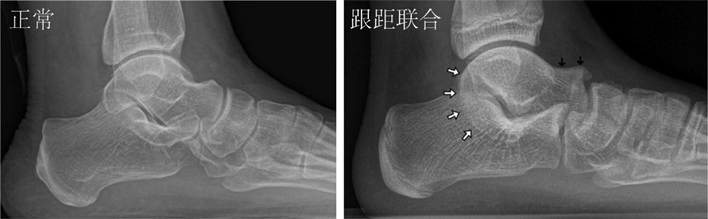

▶跟距联合:是距骨和跟骨之间出现异常的骨性或纤维性连接,是最常见的类型,约占所有跗骨联合的50%。

图2:跟距联合示意图